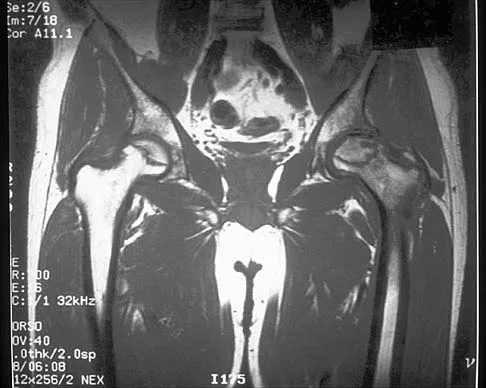

A patient undergoes hip arthroscopy, and the pathology is seen in Figure 18. What is the most likely diagnosis?